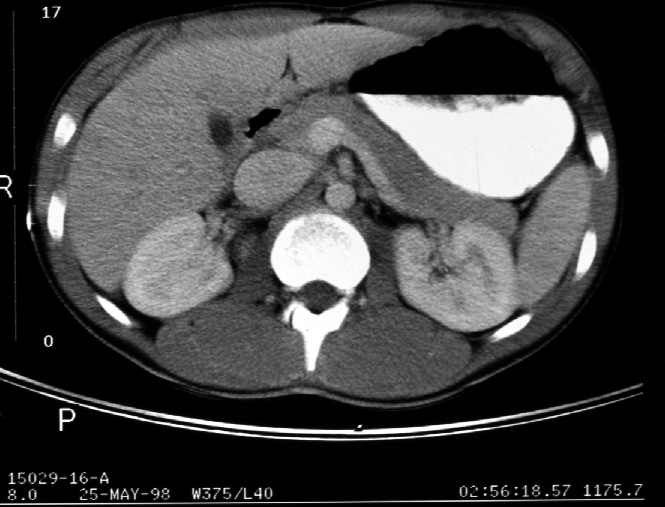

Identify -- stomach, liver, right kidney, left kidney, aorta, inferior

vena cava, portal vein, pancreas, superior mesenteric artery, gall bladder,

spleen